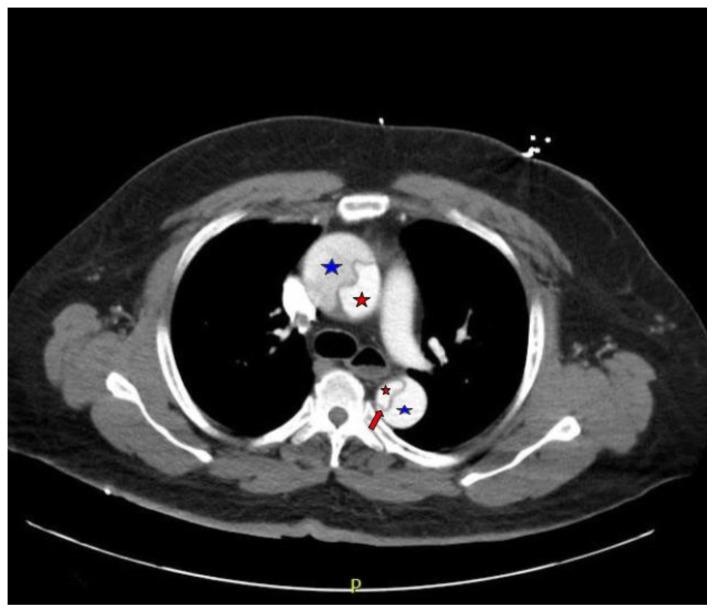

Acute aortic dissection is a life-threatening event caused by separation of the aortic layers that requires prompt management and surgical consultation. We present the case of a 53-year-old male who developed acute, severe chest pain radiating to his back at a community hospital and was transferred to a tertiary center for definitive surgical management. The patient's aortic dissection was diagnosed via computed tomography angiography. He was started on rate-control and blood pressure medications, and was admitted emergently to the operating room. Emergency physicians should obtain immediate surgical consultation, promptly start medications for rate and blood pressure control, and administer analgesia in order to stabilize their patient and decrease the shear forces that would further propagate an aortic dissection.

急性主动脉夹层是一种由主动脉各层分离引起的危及生命的事件,需要及时处理并进行外科会诊。我们报告一例53岁男性病例,该患者在社区医院出现急性、严重的胸痛并放射至背部,随后被转至三级中心进行确定性手术治疗。患者的主动脉夹层通过计算机断层扫描血管造影术确诊。他开始接受心率控制和血压药物治疗,并紧急送入手术室。急诊医生应立即进行外科会诊,迅速开始使用控制心率和血压的药物,并给予镇痛治疗,以稳定患者病情并降低会进一步加重主动脉夹层的剪切力。